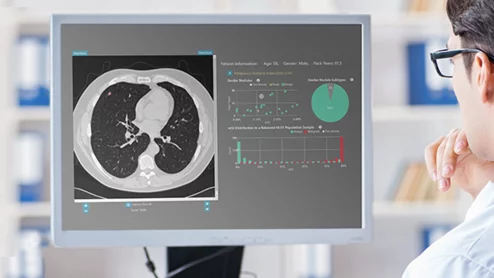

According to Heartflow, its AI offering saves health systems nearly $1,400 per patient thanks to reductions in unnecessary cardiovascular testing.